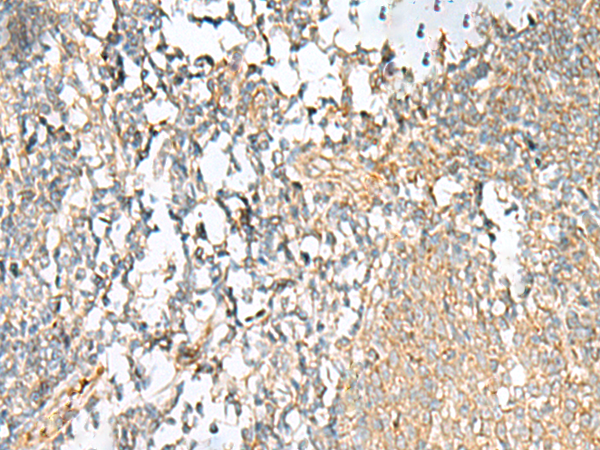

IHC positive control:

Human tonsil and Human esophagus cancer